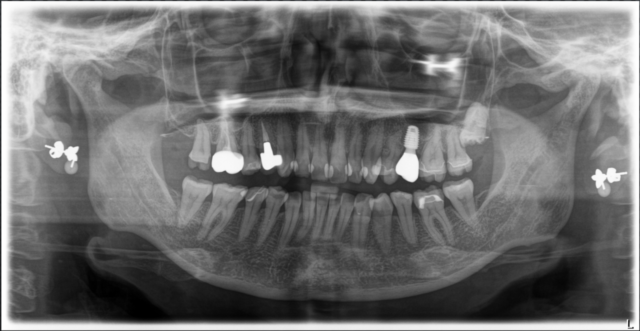

set後のレントゲン

膿疱もキレイに治っております。

術後レントゲン

-